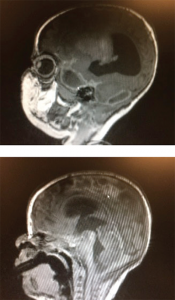

Figure 1 (TOP): Sagittal brain MRI demonstrating a focal area of ischemia (arrow) secondary to meningitis. Figure 2: Sagittal brain MRI. The ring-encasing lesion (arrow) is demonstrative of subdural empyema in the midbrain secondary to bacterial meningitis.